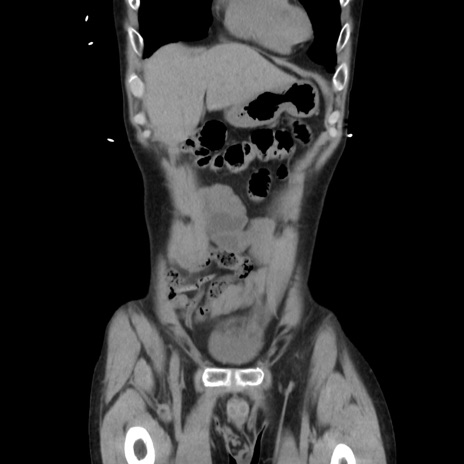

症例37(冠状断像)

【症例】40歳代 男性

【主訴】腹痛

【現病歴】4時間ほど前に電車に乗車中に臍部上より腹痛出現。徐々に増悪し起立困難となり、救急外来受診。生ものは数日食べていない。今朝お雑煮を食べた。

【身体所見】BT 36.8℃、BP 117/84mmHg、HR 91/min、SpO2 97%、苦悶様、腹部:臍上部広範囲圧痛あり、反跳痛±

【データ】WBC 8100、CRP 0.03